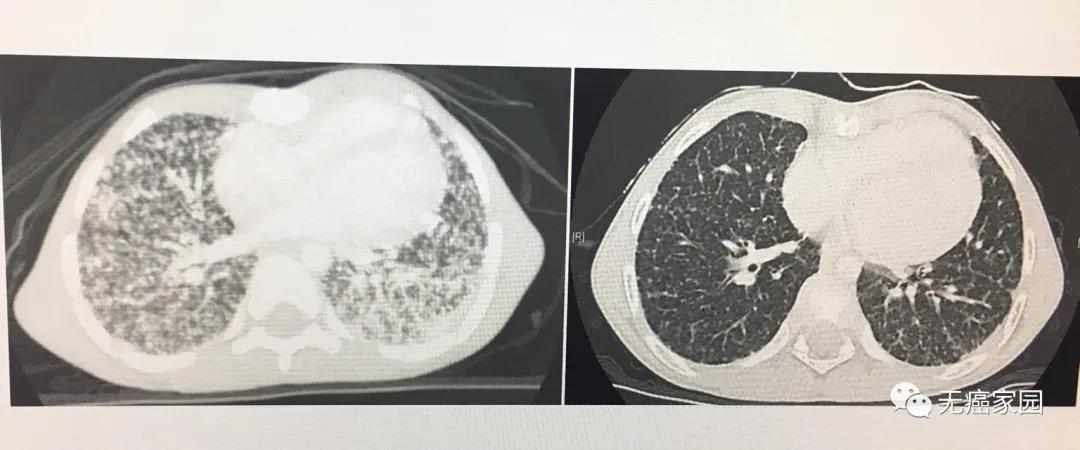

他从7月份开始使用该药,就在2个月内,大部分的肿瘤已消失——影像学检查的结果还剩下一些很小的斑点,直到8个月后,阿什顿肺部的肿瘤几乎消失了。他不再需要氧气瓶,已经能够和朋友们一起跑步、一起踢足球。

图片阿什顿最后一次扫描